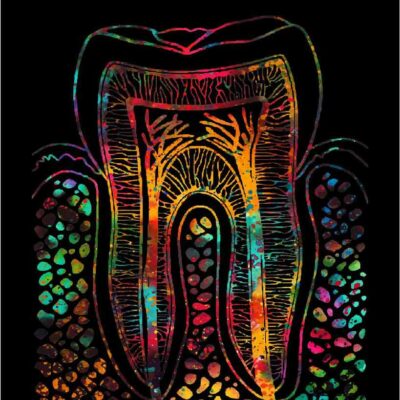

Tableaux murale pour la décoration intérieure d’un cabinet médical dentiste